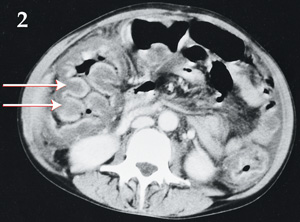

Bowel wall "thumbprinting" in pseudomembranous colitis

Med J Aust 2003; 179 (2): 107. || doi: 10.5694/j.1326-5377.2003.tb05448.x